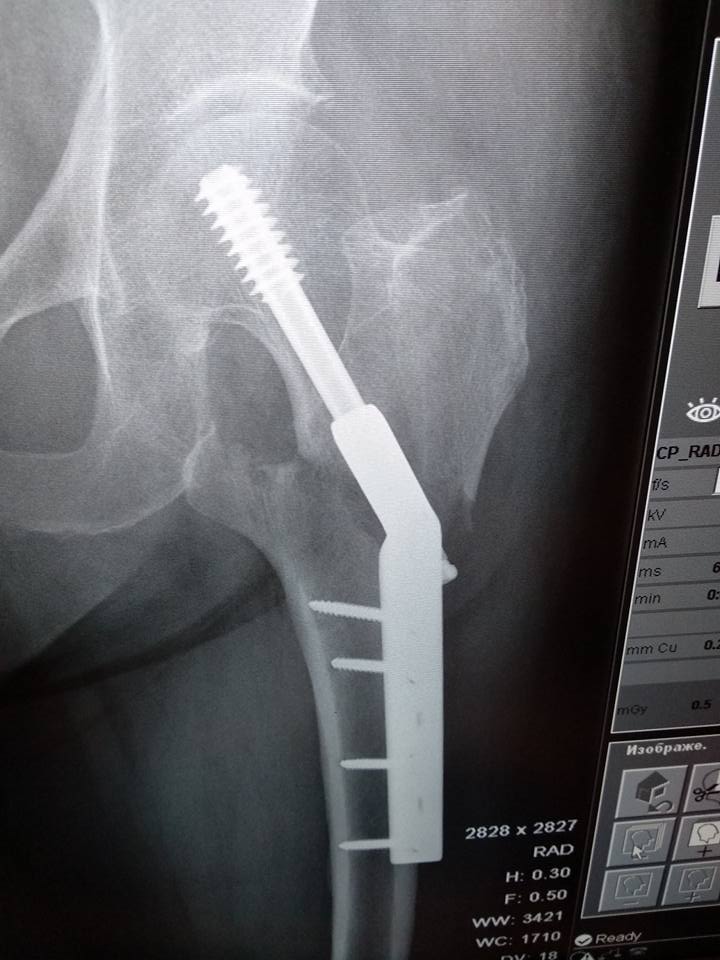

[Ortho] Межвертельный перелом после фиксации DHS

У пациентки операция неделю назад, к нам поступила с короткой выпиской и

без снимков. На контрольных рентгенограммах вот такая картина.

Непонятно, это вторичное смещение или так и было.. утверждает что не

наступала. 80 лет, сохранная, активная женщина. Нога болит, прилипшая

пятка, ротации, укорочения нет. Коллеги, какие мнения?